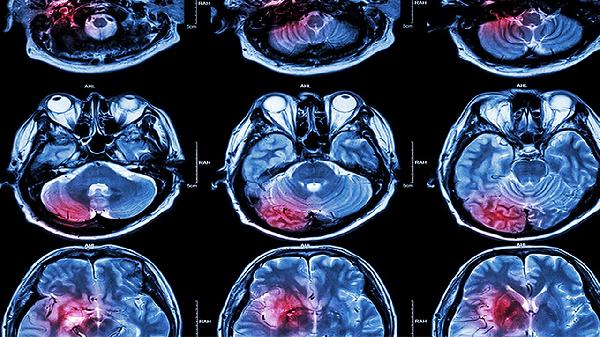

单眼短暂性黑矇或双眼视野缺损常见于后循环缺血,表现为眼前黑影遮挡、视物成双,持续5-30分钟恢复。糖尿病患者出现该症状需警惕视网膜动脉栓塞,应避免剧烈转头,可配合银杏叶提取物片改善微循环。

突发旋转性眩晕伴恶心呕吐,可能与椎基底动脉供血不足相关,常在转头或体位变化时诱发。患者行走时易向患侧偏斜,需排除耳石症,发作期可卧床休息,医生可能开具盐酸氟桂利嗪胶囊控制症状。